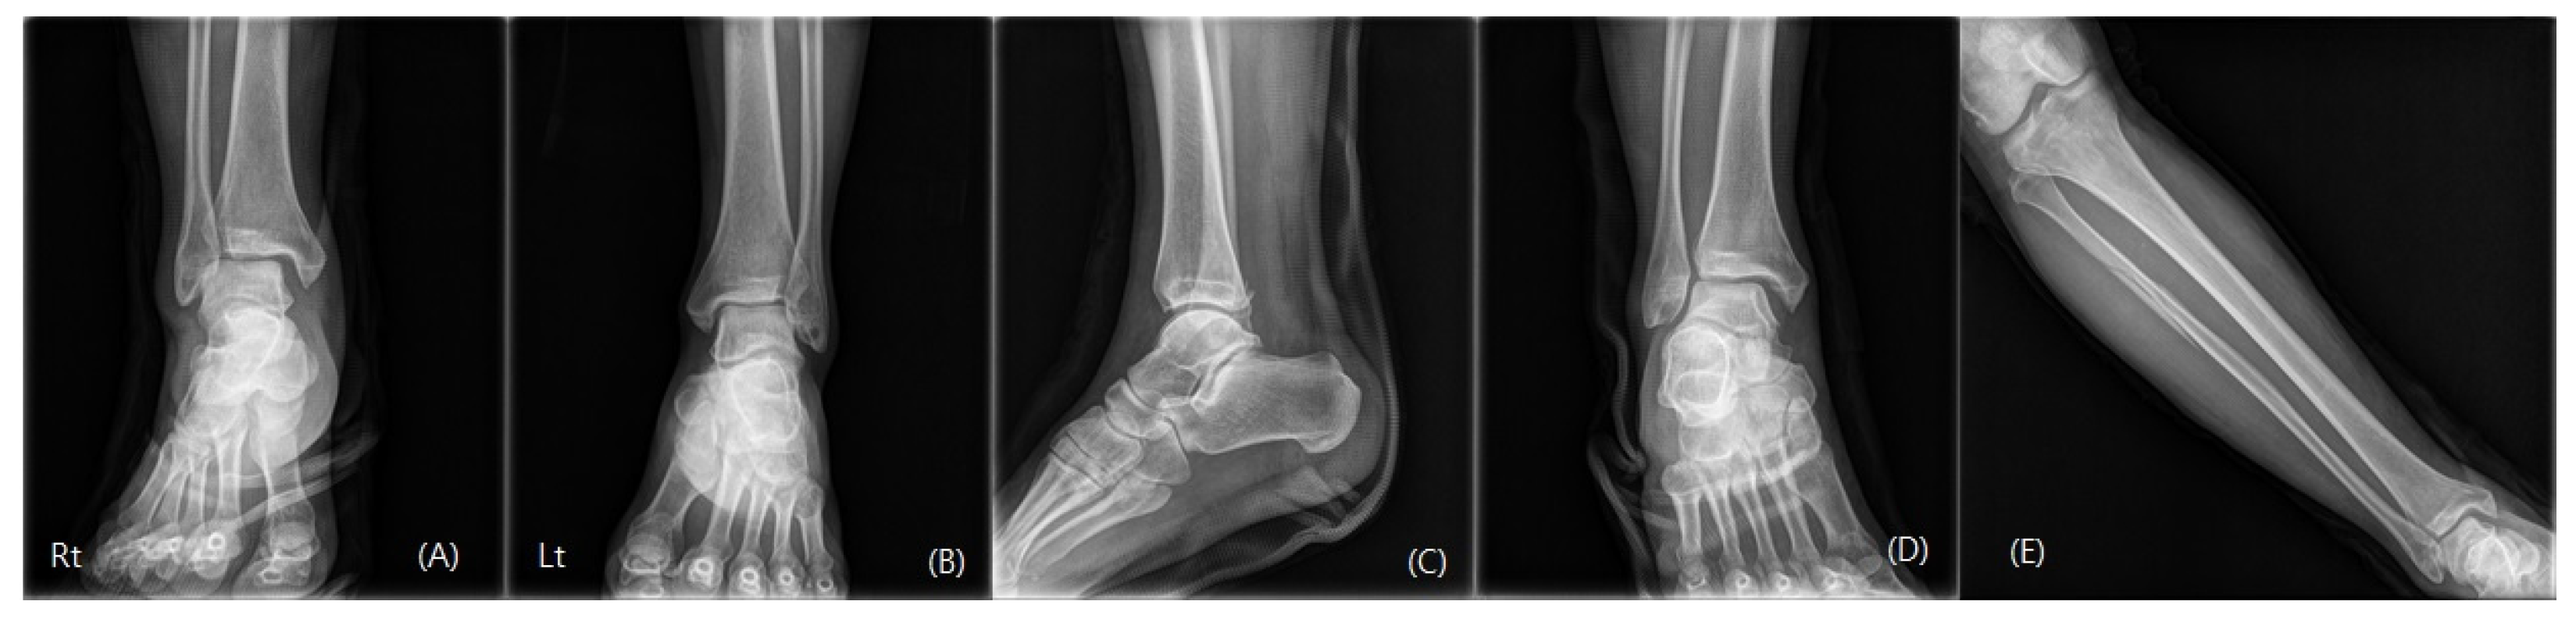

2. Case Presentation